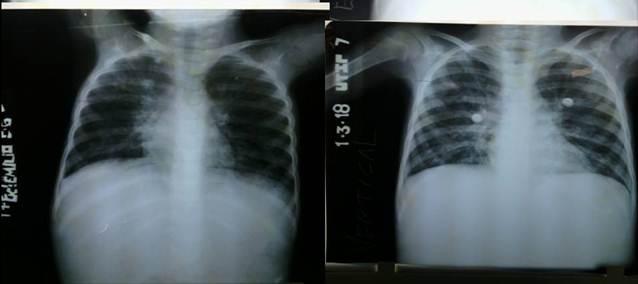

Se indicó endoscopia digestiva superior con el objetivo de tomar muestras de biopsia de duodeno para estudio de malabsorción pero la niña presentaba síntomas respiratorios persistentes como tos húmeda, productiva que fue interpretada como atopia respiratoria que en una ocasión fue agravada por neumonía adquirida en la comunidad que necesitó ingreso en unidad de cuidados intensivos (Figura 2).

Rayos X de tórax: (Figura 3).